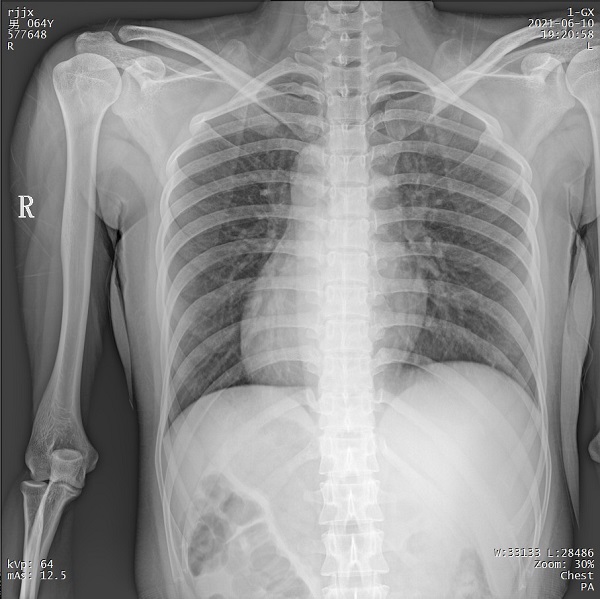

四、創傷患者可通過床旁攝影獲取高質量圖像

PLX5500憑借充沛的射線輸出,能夠在床旁對各體型創傷患者的各部位進行拍攝,輸出清晰圖像,輔助醫生進行精確診斷。患者無需帶傷前往放射科拍攝,降低二次傷害風險。